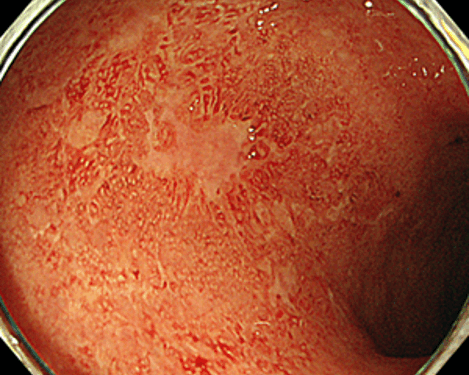

活動期(軽度)潰瘍性大腸炎の像

それよりも炎症の活動性が高く、潰瘍を認める像です。(血管透見消失・粘膜発赤・小黄白色点散在)